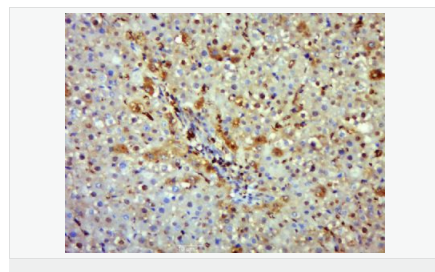

image.png